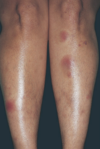

When covering for cellulitis, you cover for what organisms?

Group A strep (pyogenes) and MSSA

Tx of choice for cellulitis

1st gen cephalosporins